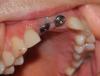

Жертва имплантолога Опубликовано 28 ноября, 2012 Поделиться Опубликовано 28 ноября, 2012 Имплантировала два передних зуба.Фото результата работы имплантолога прилагаю. Есть КТ, но и так явно видно, что импланты установлены криво, под разными углами к вертикальной оси. Один завален внутрь, верхняя часть находится в десне. Другой смотрит на улицу. Установка металлокерамики на эти импланты была почти не возможна. На счастье протезист оказался кудесником и умудрился обуть это в металлокерамику, визуально вполне приличную. Но о том, что бы ею кусать не было и речи. Прослужила такая конструкция два года.В настоящий момент оба импланта требуют удаления и замены (подвижность, трещина надкостницы). Была на приёме у этого (моего) имплантолога. Она объяснила, что это нормально, если у пациента зубы не правильные, а импланты установлены криво для моей же пользы и что клиника готова всё переставить всего за ~ 150 000 р. И что уже через ~ 12 месяцев всё будет как новое. Неужели срок службы имплантов, установка которых тогда стоила ~ 140 000 р. составляет всего 2 года и халтура никак не доказуема и не наказуема? Ссылка на комментарий